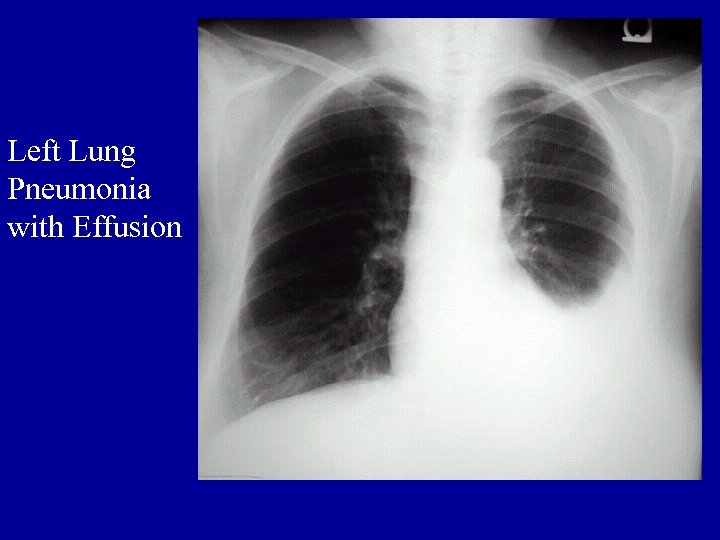

Other Laboratory Findings in ARF CXR Abnormalities Complete Blood Count (look at WBC and Hgb, which may suggest chronic hypoxia) Electrolyte Abnormalities (look at bicarbonate)

Left Lung Pneumonia with Effusion